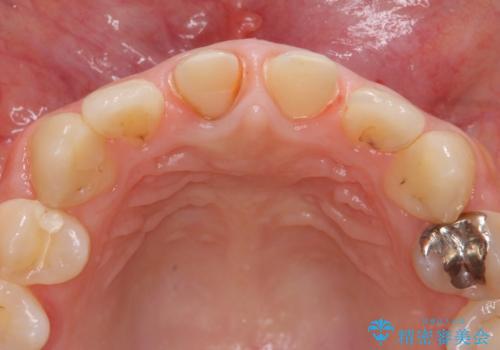

虫歯の徹底的な除去、根管治療を行いセラミック治療に入る前の環境をしっかりと整えたのち審美的なジルコニアセラミックで治療を仕上げました。

- 26.4万円(仮歯×2・ファイバーコア・ジルコニアクラウン×2)費用は治療当時の料金となります